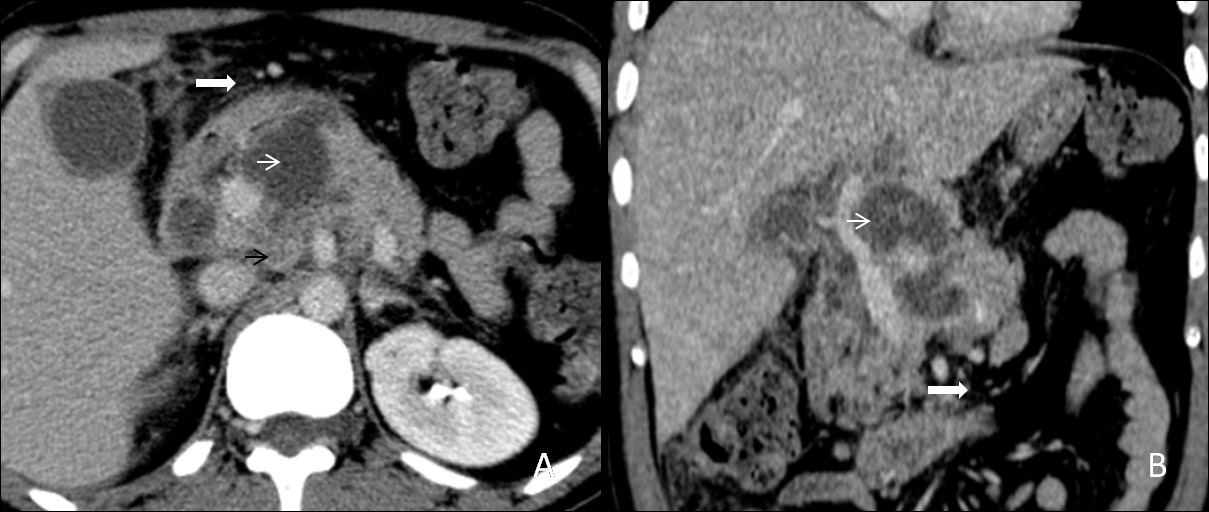

Pancreatic tuberculosis

Isolated tuberculosis of the pancreas is rare, even in countries with a high prevalence of tuberculosis. Pancreatic tuberculosis represents solitary or multiple lesions with multiple necrotic areas. It usually occupies the pancreatic body or head, (Figure 9A,9B) and peripancreatic lymphadenopathy can also be found. The cystic component appears hypoechoic (sometimes hypo-isoechoic) on ultrasound and hypodense on CT scan [9].

Figure 9: (A,B) A 30 years old male patient with constant and chronic vague pain in the epigastric region undergone a contrastenhanced computed tomography of abdomen. The axial and reformatted coronal plane images from the venous phase show a bulky pancreas having intraparenchymal collections (white arrows), peripancreatic fat stranding (thick white arrows) and enlarged lymph nodes (black arrow). It was later diagnosed as pancreatic tuberculosis on fine-needle aspiration from the cystic component. Standard antituberculous therapy involving at least four drugs remains the cornerstone of the treatment. Therefore, the patient has been on ATT for the last three months.